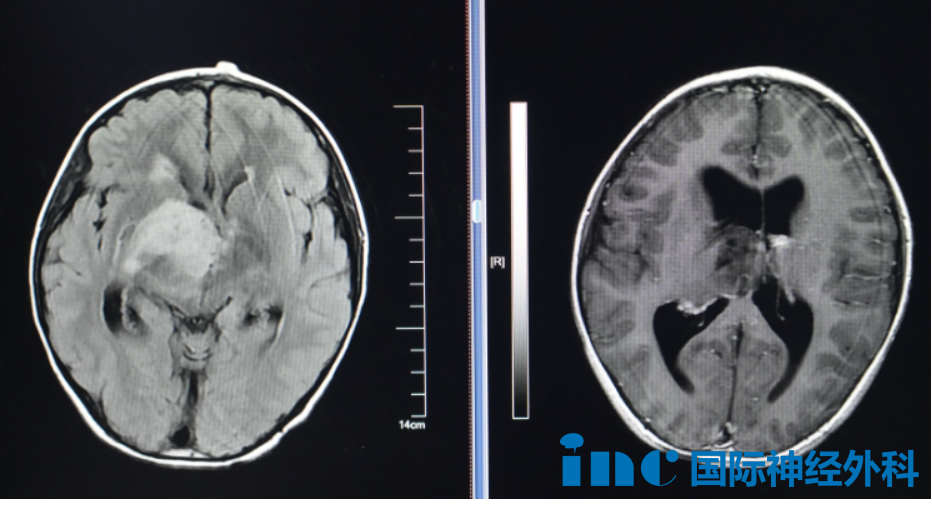

类似情况也出现在8岁患儿小航身上。影像检查显示右侧丘脑与基底节区占位病变,病灶尺寸约4.0cm×4.7cm×4.8cm,高度怀疑为弥漫性胶质瘤。

患儿临床表现包括记忆力减退、注意力障碍及饮水呛咳等症状。面诊时家属焦虑询问:"肿瘤恶性可能性多大?巴教授能否为他手术?"他们未曾预料到肿瘤已发展至如此规模。

巴教授详细评估后明确指征:患儿具有明确手术指征,需尽快干预,不宜延误。关于病理类型,教授表示可能为低级别胶质瘤,但最终诊断需依赖术后病理学确认。